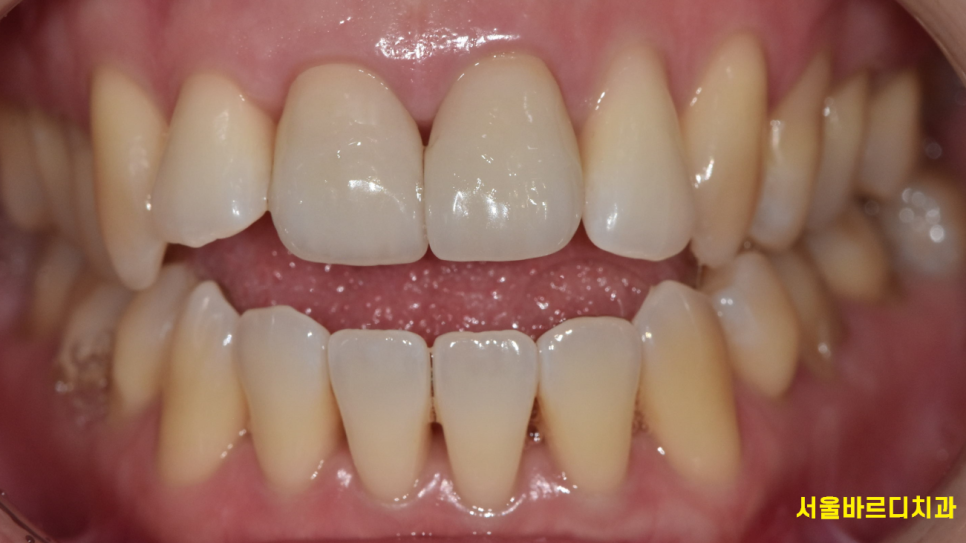

241022 겉으로는 전혀 치근흡수가 일어났는지 알 수 없어요